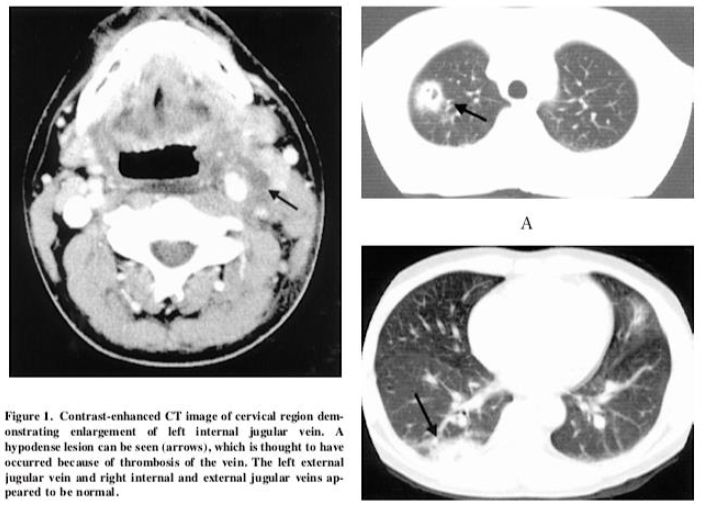

另一篇文献报道一例32岁男性患者,发热、咽痛、关节痛和颈部疼痛及活动受限4天。颈部左侧疼痛肿块,颈部CT提示颈静脉血栓,胸部CT提示肺脓肿,血培养发现不解糖卟啉单胞菌。

图片

图片来源:Intern Med, 2005,44(4):350-353.

该患者的颈部CT提示左颈静脉充盈缺损,长度约为62 mm,考虑血栓形成。